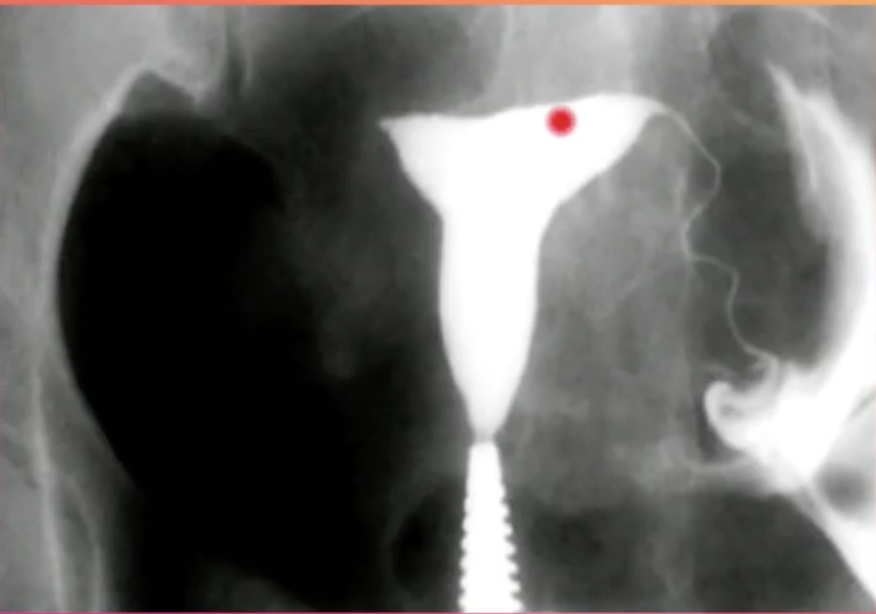

Q

Qual Exame e Qual o Achado?

A

Histerossalpingografia = Pott Positivo a Esquerda